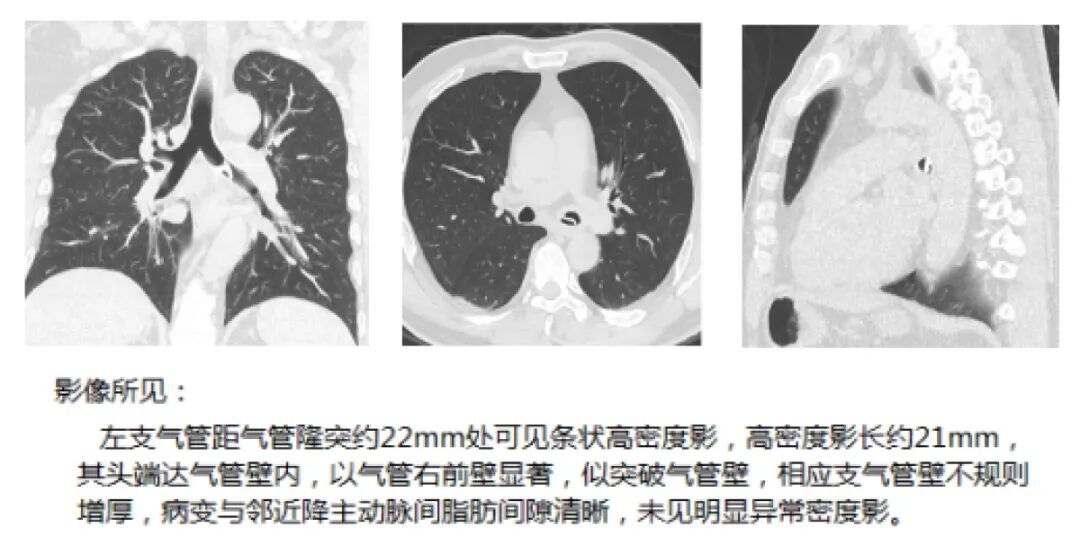

“这根鱼骨呈三角形,异常锋利,牢牢地卡在气道中。”呼吸内镜中心主任王振静介绍,“患者的气管黏膜已经充血水肿、糜烂,如果再不取出,可能导致气管穿孔、纵隔感染,甚至引发大出血,后果不堪设想。”呼吸内镜中心、医学影像科、麻醉科迅速联动,实施了无痛气管镜下异物取出术,才将这根骨刺成功取出。